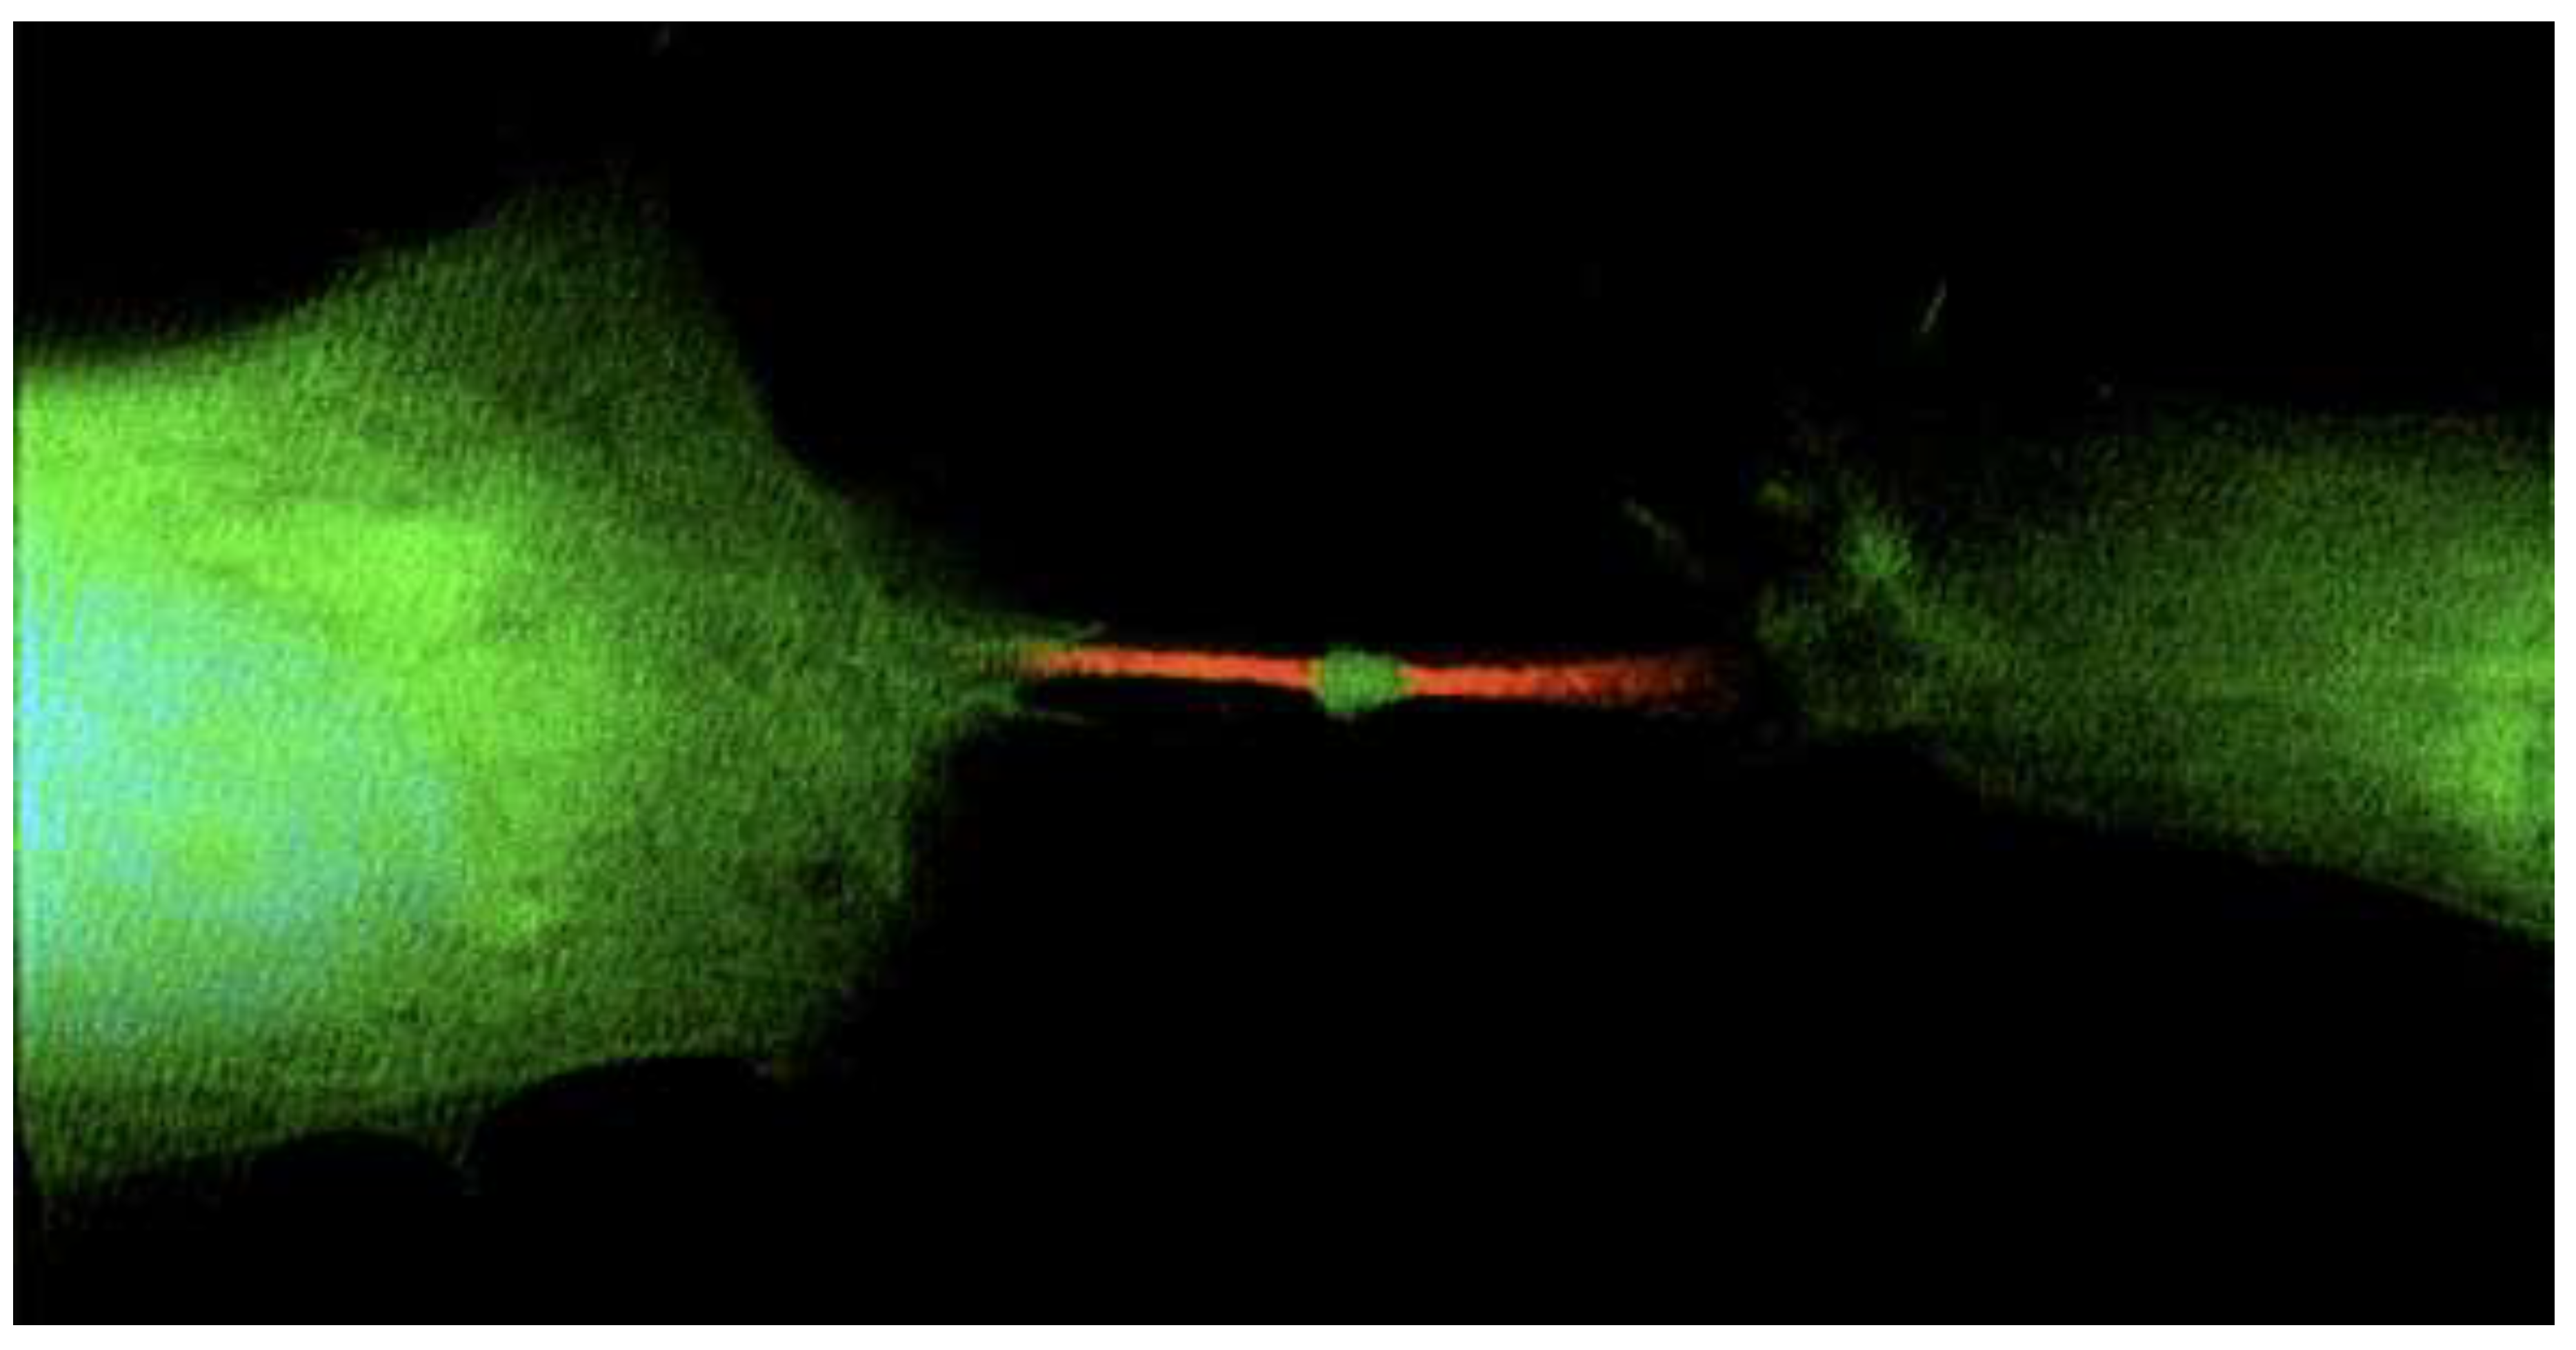

Researchers have identified a gene, called Arc, that plays a role in modulating cell activity. This gene packs functional genetic material with the power to change the fate of other cells by transferring genetic information, including turning them into cancer, [26]. [Figure 1].

Figure 1. The memory gene is important for all cells to communicate RNA information.